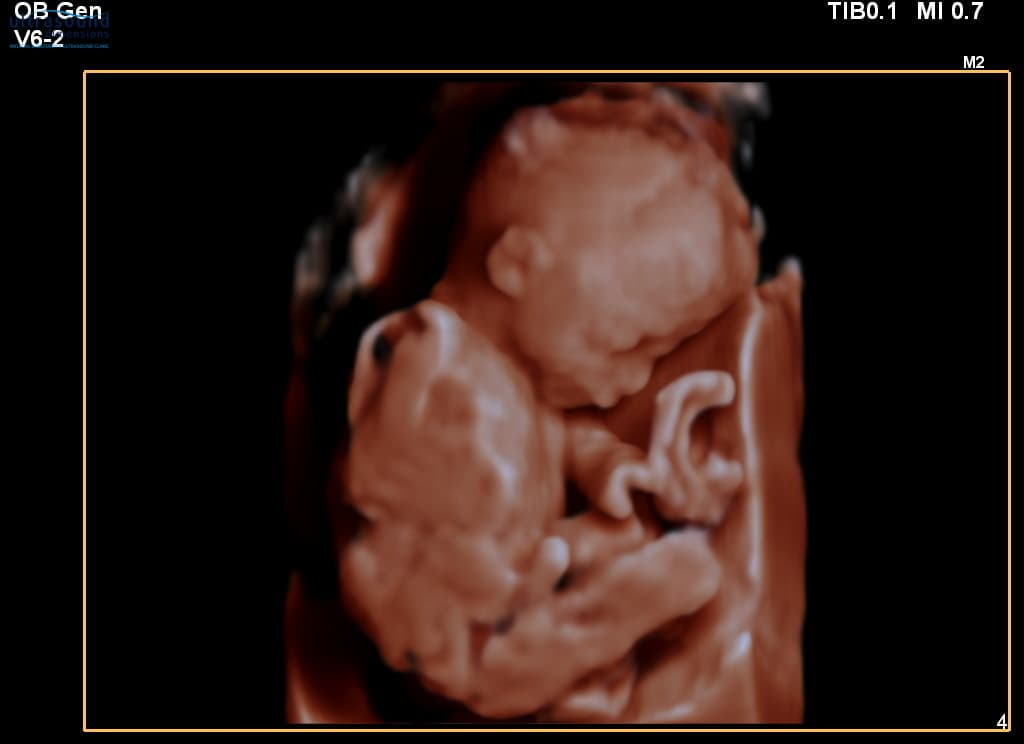

This adorable baby was captured during a Well Baby Scan at 20 weeks gestation.

At 20 weeks, your baby is about the size of a banana and you can see:

- Detailed facial features - nose, lips, eyes

- Fingers and toes - all clearly visible

- Active movement - kicks, stretches, and somersaults

- Developing organs - all systems taking shape